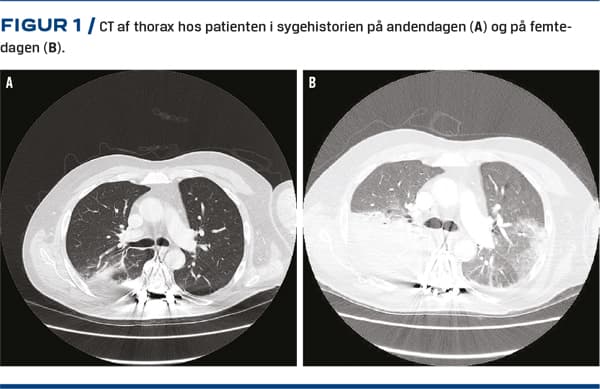

En 66-årig mand med hypertension blev indlagt på baggrund af almen sygdomsfornemmelse, feber og opkastninger gennem et døgn. Hans søn havde haft influenzalignende symptomer to uger før patientens symptomdebut. Ved ankomsten var blodtrykket 150/74 mmHg, pulsen 78 slag/min, temperaturen 39,6 °C, respirationsfrekvensen 14 pr. min og SpO2 95%. Lunge- og hjertestetoskopi samt neurologisk undersøgelse var upåfaldende. Paraklinisk fandtes CRP-niveauet forhøjet til 91 mg/l (referenceværdi < 10 mg/l), leukocyttal inden for normalområdet og let anæmi. En røntgenundersøgelse af thorax viste normale forhold. Der blev påbegyndt intravenøst indgivet piperacillin/tazobactam på mistanke om infektion uden kendt fokus. CT af thorax og abdomen på andendagen viste pneumonisk udseende bilaterale infiltrater (Figur 1A). Grundet vedvarende feber og stigende CRP-niveau til 200 mg/l blev der på tredjedagen tillagt clarithromycin. Procalcitoninniveauet var lavt under hele forløbet. Mikrobiologiske undersøgelser af blod, trakealsug til undersøgelse for almindelig mikrobiologi og atypiske bakterier (Mycoplasma pneumoniae, Chlamydia pneumoniae og Legionella pneumophila), samt legionella- og pneumokok-urinantigen var alle negative. På dag fem fik patienten hypoksisk respirationsinsufficiens med behov for 15 l ilt med high flow og continuous positive airway pressure. CT-angiografi udelukkede lungeemboli, men viste betydelig progression af de infiltrative forandringer og nytilkommet pleuravæske (Figur 1B), der indeholdt 2.130 × 106 celler/l med monocytær overvægt og protein på 45 g/l, men intet bakterielt DNA. Dette blev tolket som ekssudat og parapneumonisk effusion. På dag seks fandtes der leverpåvirkning (referenceværdier i parentes): transaminaser 134 E/l (14-45 E/l), basisk fosfatase 189 E/l (35-105 E/l), laktatdehydrogenase 489 E/l (105-205 E/l) og albumin 18 g/l (36-48 g/l).